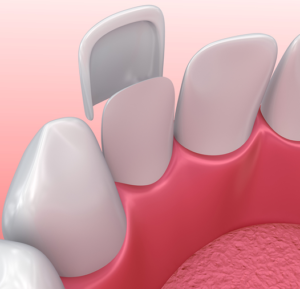

- Veneer toàn sứ: Mài ít mô răng, dán sứ vào mặt ngoài của răng. Loại phục hình này cần chú ít khi ăn nhai do chịu lực ít.